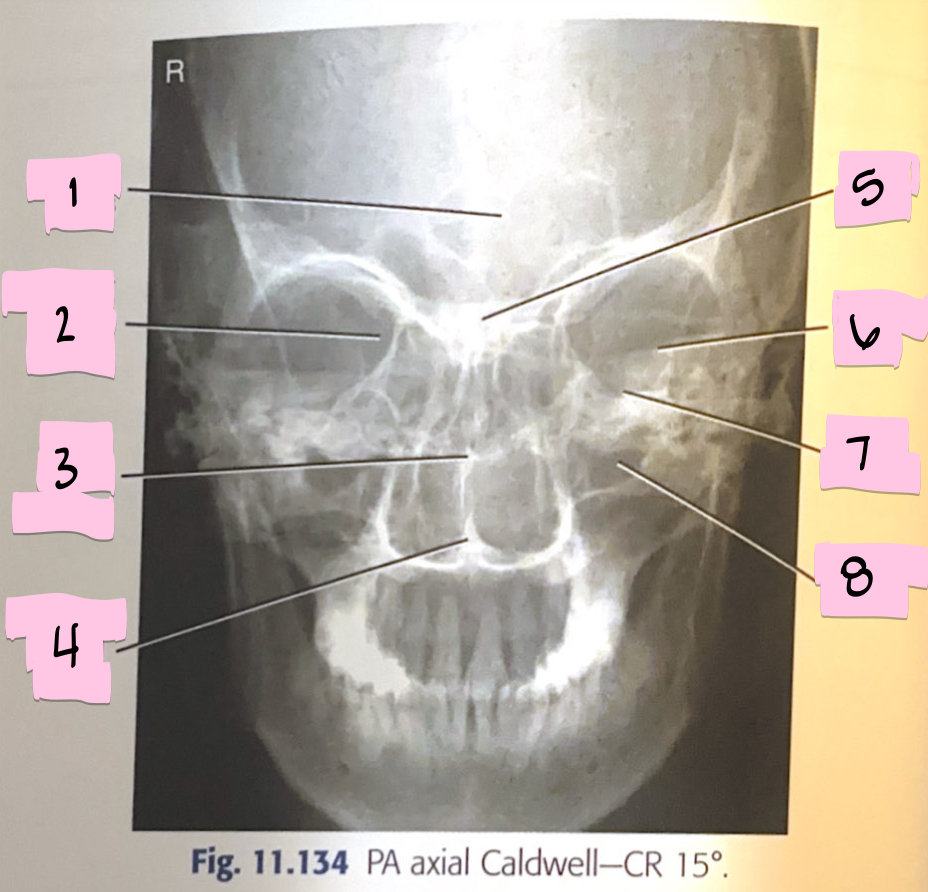

What is 1 pointing to?

Frontal sinus

What is 2 pointing to?

Superior orbital fissure

What is 3 pointing to?

Bony nasal septum

What is 4 pointing to?

Anterior nasal spine

What is 5 pointing to?

Crista galli

What is 6 pointing to?

Petrous ridge

What is 7 pointing to?

Floor of orbit

What is 8 pointing to?

Maxillary sinus